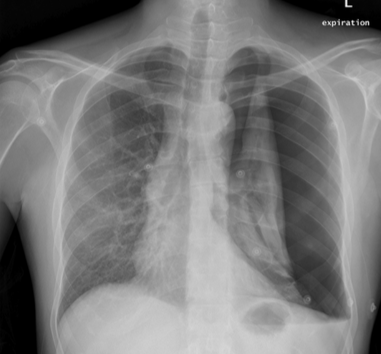

A tall, young healthy male presents with acute onset dyspnoea associated with unilateral chest pain and tracheal deviation to the opposite side

Tension pneumothorax

Causes: spontaneous (as here), traumatic, iatrogenic